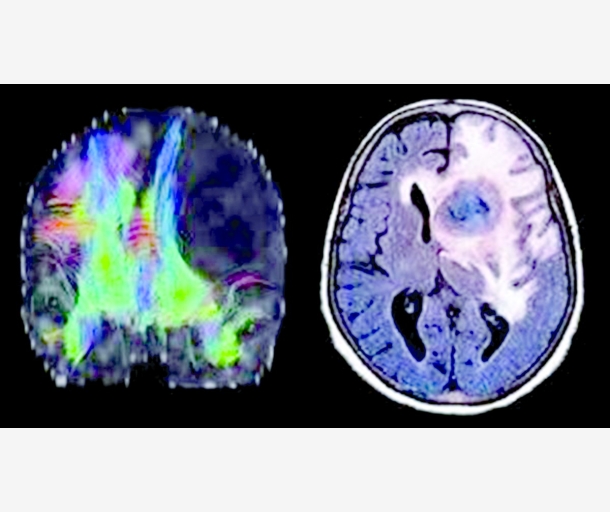

جهاز لاسلكي لقتل أورام الدماغ الفتاكة